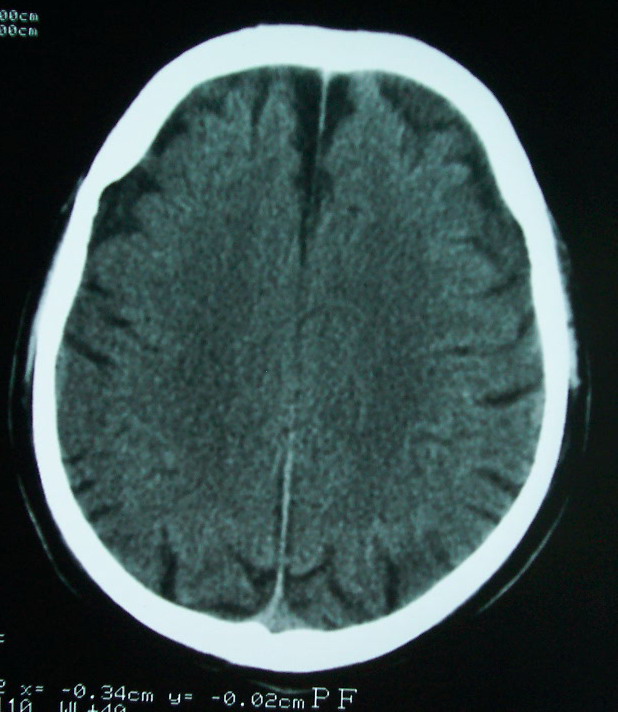

以下是引用余辉在2009-4-15 20:49:00的发言:[br]右侧病灶发生于冠状缝区,但额骨左侧鳞也有病灶,病灶区脑沟裂增宽(有脑萎缩征像,把这个征像放在颅骨病变一起考虑可能有点牵强),是否可能是板障血管畸形所致谢?抑或是嗜酸性肉芽肿或蛛网膜粒压迹那类东西?

以下是引用whzht在2009-4-15 20:57:00的发言:[br]1、额骨改变,考虑蛛网膜粒压迹;[br]2、脑萎缩。